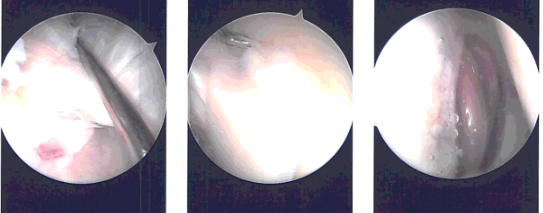

Intraoperative images

Time-out was called. Preoperative antibiotic was given. A lateral incision was given for the entry portal. Scope was entered. Patellofemoral compartment showed grade 1 to grade 2 osteoarthritic changes.

A medical entry portal was made using a spinal needle. Examination of the medial compartment showed a complex tear of the posterior horn of the medial meniscus. The tear was debrided. Medial meniscus was debrided with the use of straight biter, upbiter, and shaver.

Examination of the intercondylar notch showed intact ACL with degeneration. Examination of the lateral compartment showed medial frayed margins of the lateral meniscus which was debrided with the use of upbiter as well as the shaver.

The debridement of the patellofemoral joint was done and chondroplasty was performed with the use of the thermal wand and shaver. Suprapatellar plica was permanent which was removed with the use of a thermal wand.

The scope was entered from the medial portal and instruments were entered from the lateral portal to complete the medial meniscectomy.

Final pictures were taken and saved. The knee was thoroughly irrigated. The knee was drained. Closure was done with use of the # 3-0 nylon. A 9 cc of Naropin 0.5% mixed with 40 mg of Depo-Medrol was injected in the knee.